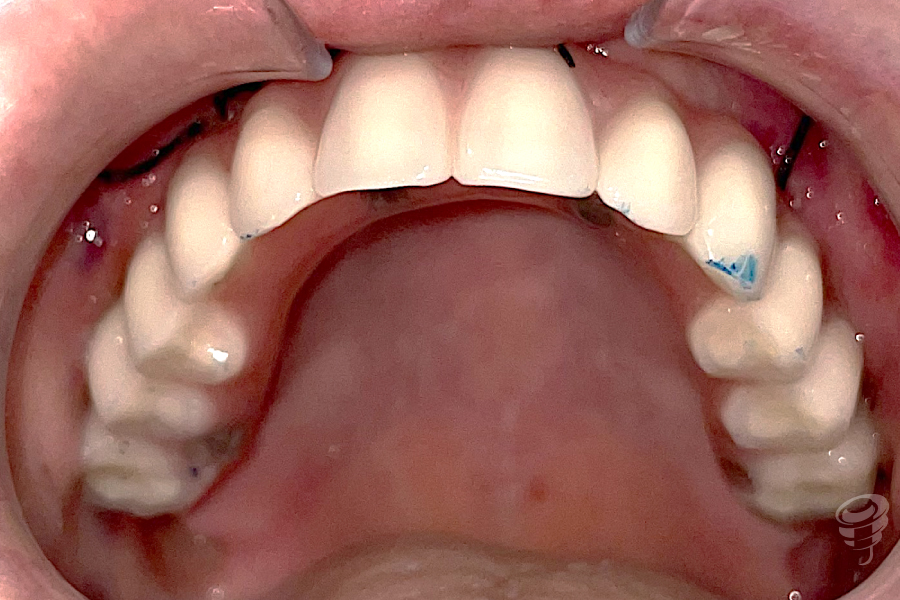

Orto postoperatorio inmediato + Carga inmediata. (Imagen 10 y 11)

Imagen 12

Imagen 13

Orto a los 3 años de evolución + Prótesis definitiva. (Imagen 12 y 13)